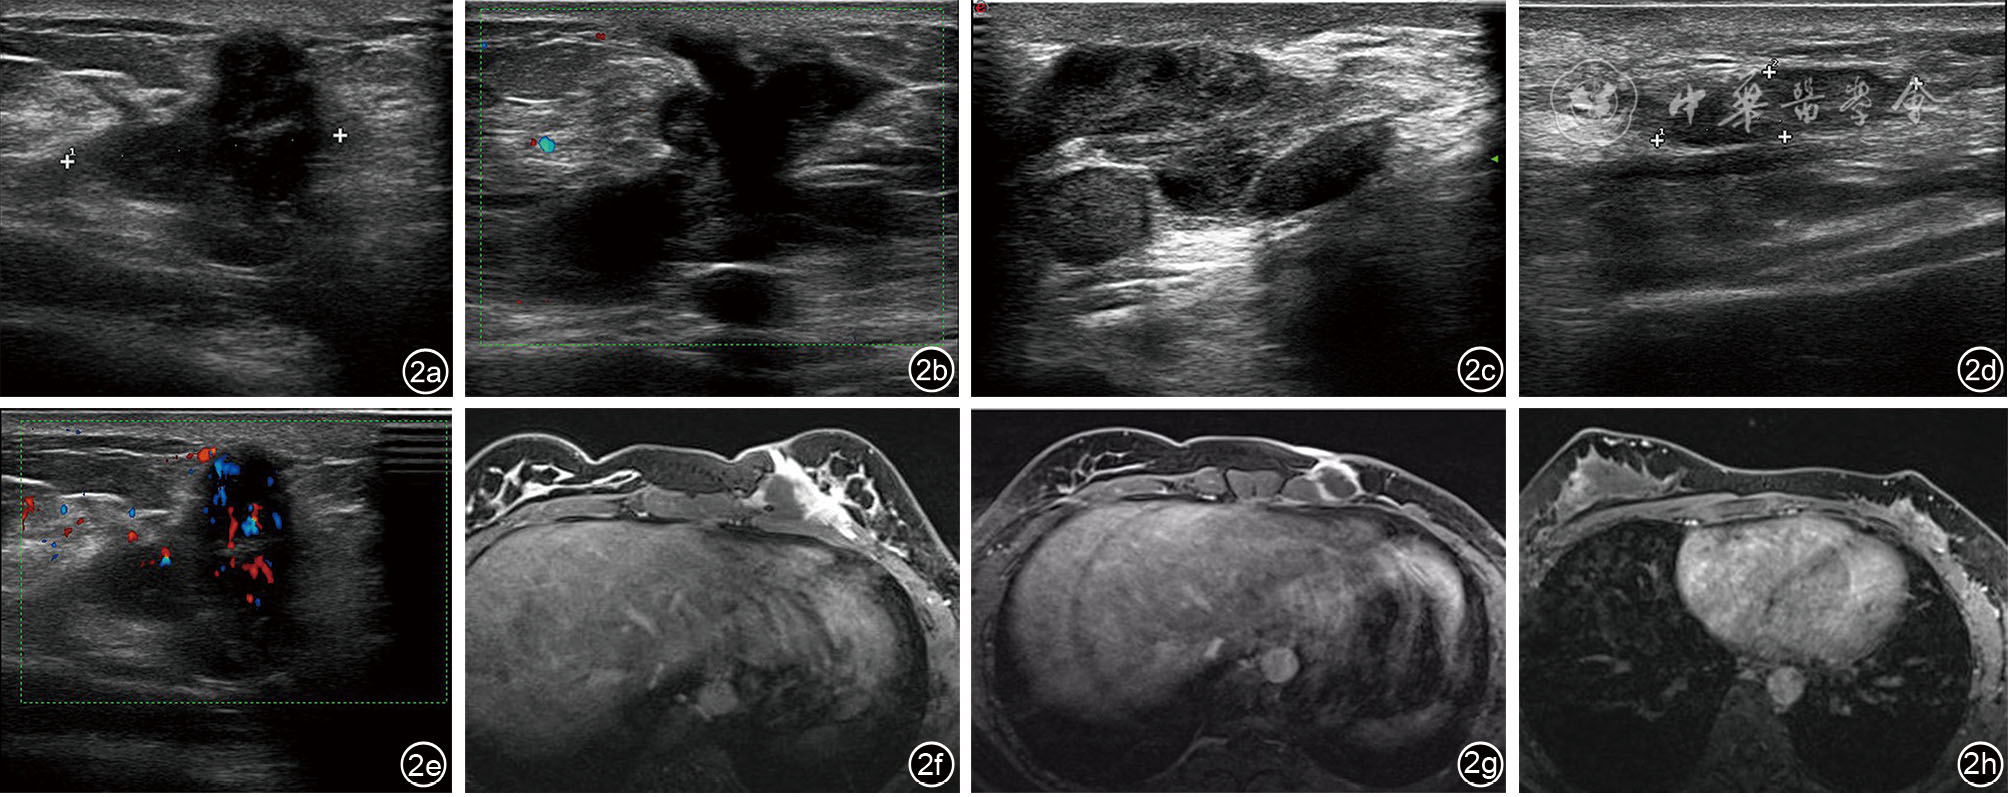

Ng WL, Teoh SY, See MH, et al. Desmoid type fibromatosis of the breast masquerading as breast carcinoma: value of dynamic magnetic resonance imaging and its correlation [J]. Eur J Breast Health, 2021, 17(2): 197-199.

董叶, 彭晓静, 邓晶, 等. 高频超声诊断侵袭性纤维瘤病的应用价值 [J]. 临床超声医学杂志, 2021, 23(1): 69-72.

宗晴晴, 邓晶, 许迪. 乳腺纤维瘤病超声表现与病理结果对照研究及误诊分析 [J]. 肿瘤影像学, 2019, 28(6): 384-389.

Nakazono T, Satoh T, Hamamoto T, et al. Dynamic MRI of fibromatosis of the breast [J]. AJR Am J Roentgenol, 2003, 181(6): 1718-1719.